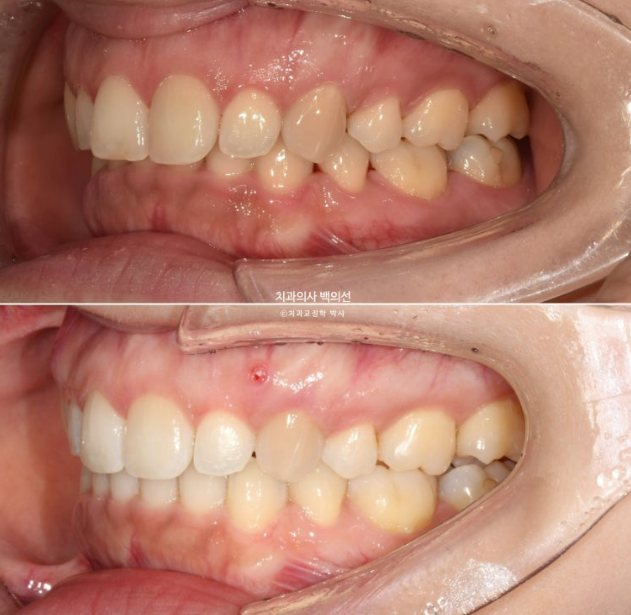

24.03~25.04

정돈된 스마일라인

깔끔한 앞니 각도

내려온 윗니에 아랫입술이 걸려 잘 다물어지지 않던 입술부전증이 해소가 되었습니다. 이제 편하게 입이 다물리죠